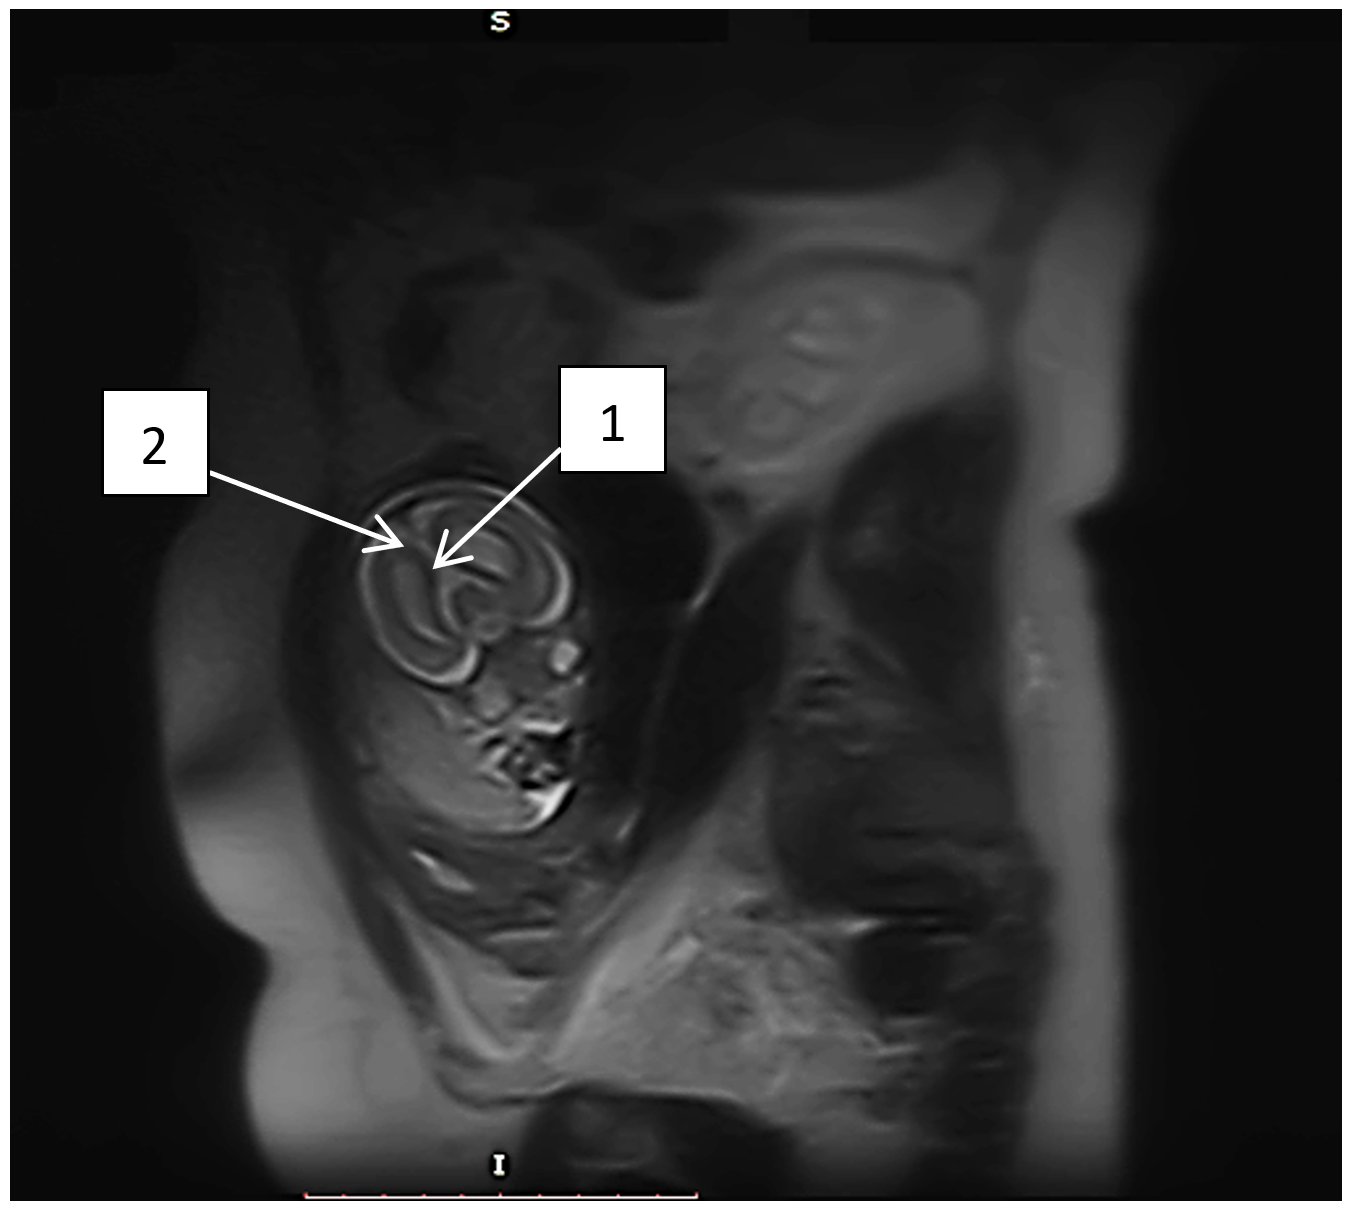

Рисунок 2 - МРТ плода в сагиттальной проекции Т2 ВИ:

1 - агенезия мозолистого тела; 2 - расширение межполушарной щели